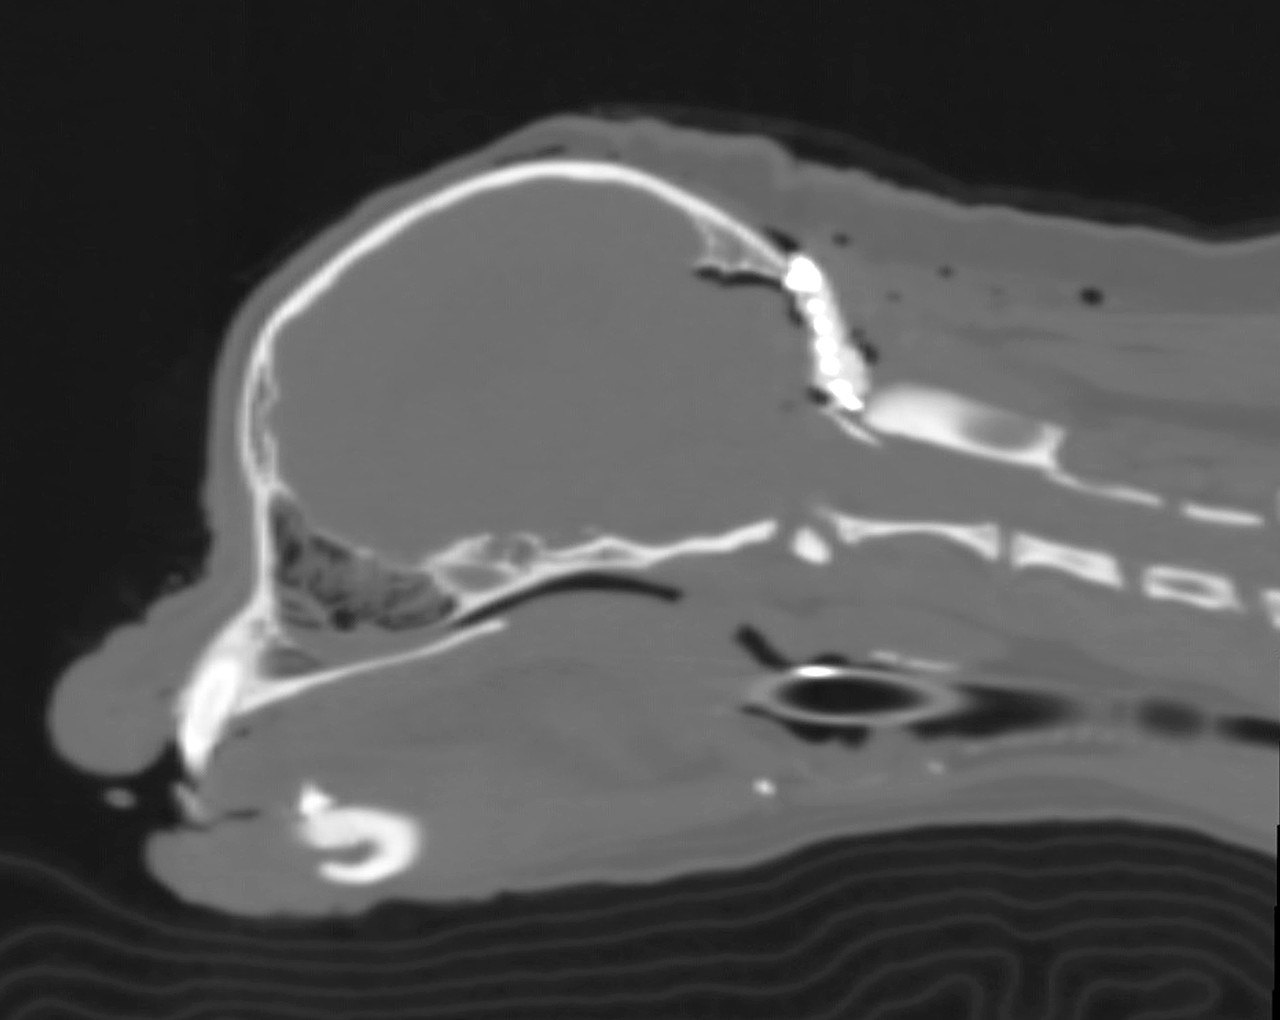

뇌 안에 뇌척수액이 고여서 뇌실이 비정상적으로 커지는 질환입니다.

인지기능장애, 시력 및 청력 소실, 발작 등 대뇌 관련 이상 증상을 보일 수 있습니다.

두개골의 기형 등에 의해 두개강 내부 공간이 작아져서 뇌조직이 압박 받아 다양한 증상이 발현되는 질환입니다.

척수공동증이나 뇌수두증 같은 2차 질환으로 이어질 수 있습니다.